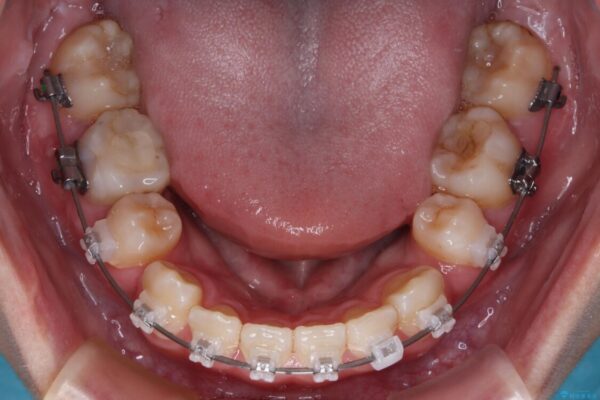

治療後

• 転勤でも安心して治療継続 抜歯スペース閉鎖と深い噛み合わせ改善のワイヤー矯正 治療後画像